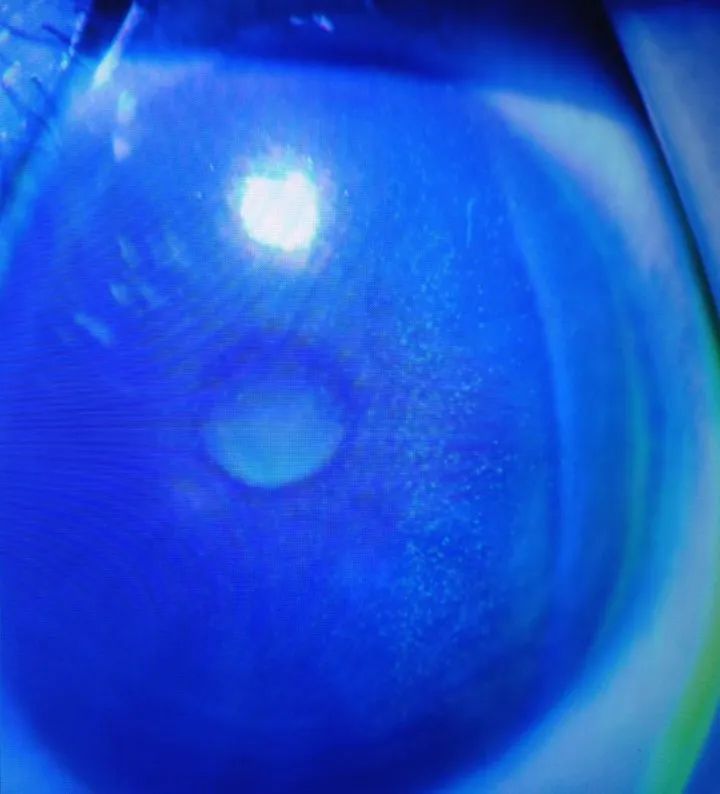

图注:角膜荧光染色发现弥漫性点状着染(点点绿色就是角膜上皮缺损的地方)